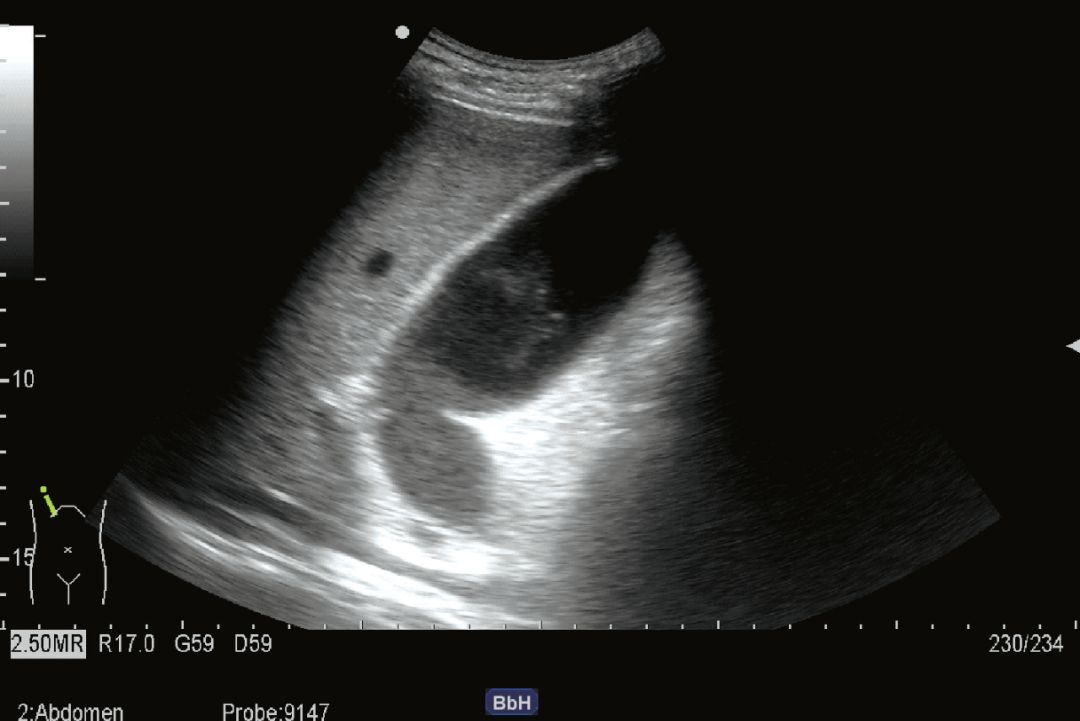

(2) 病例

1) 病史:患者男,49岁,进餐后右上腹剧烈疼痛。体温38.7℃。

2) 超声描述:胆囊体积明显增大,显张力,胆囊壁毛糙增厚,胆汁透声差,可见中低及中等回声光点淤积。胆囊窝可见线样液性暗区。

3) 超声诊断:急性胆囊炎、胆汁淤积。